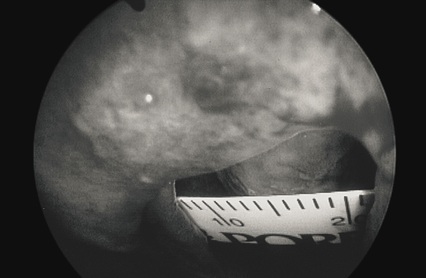

1. 測量:可先用尺和內視鏡確立大小與範圍,方便與病患溝通。